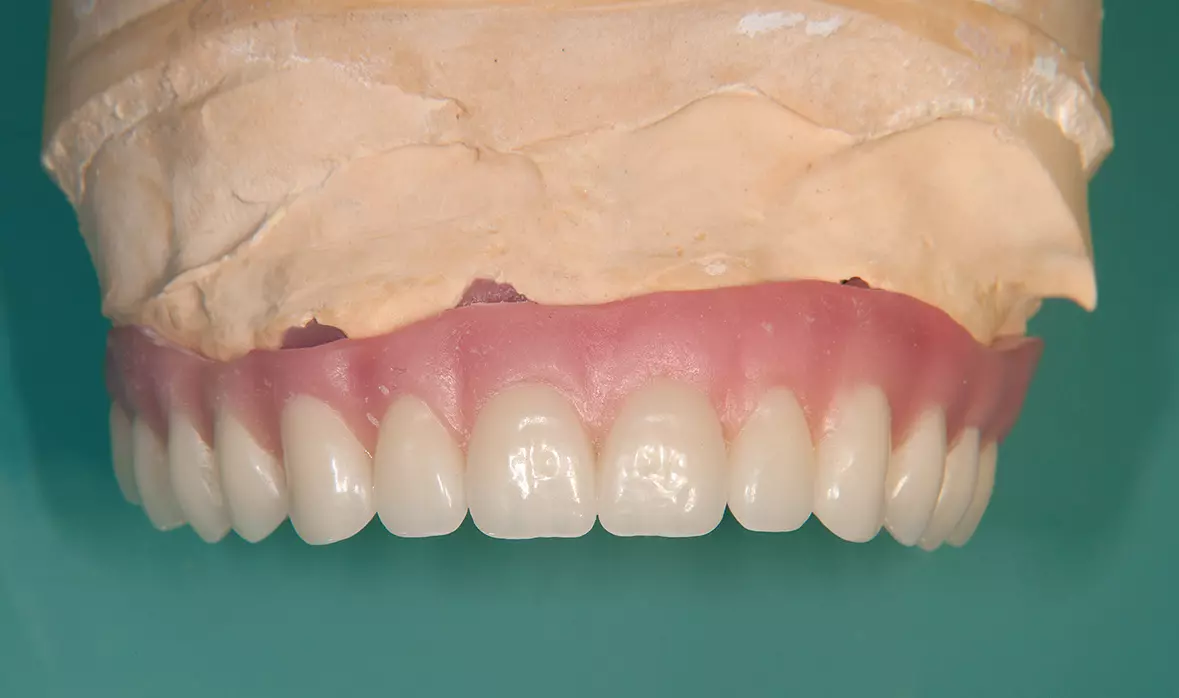

Abb. 40: Fertige Prothese. Dr. Michael Leistner

Abb. 40: Fertige Prothese.